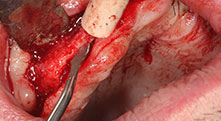

Bratu: Wir bevorzugen Knochenentnahmen von der Linea obliqua externa des posterioren Unterkiefers, nicht aus der interforaminalen Region. Nach der Weichgewebsinzision verwenden wir die neuen Sägen, um den Umfang der Knochenentnahme zu definieren. Wir erledigen damit in fast 80 Prozent der Fälle auch die gesamte Präparation. Zusätzlich verwenden wir eventuell andere Piezo-Instrumente und zuletzt einen Meißel, um den Block zu mobilisieren. Das ist für uns eine sehr effektive Operationstechnik.

Bratu: Wir augmentieren im seitlichen Unterkiefer gern mit der Sandwich-Technik. Dabei wird ein Knochendeckel mit der Piezosäge präpariert und das krestale Fragment mit Mikroschrauben fixiert. Dazwischen platzieren wir eine Mischung aus autologem Knochen und xenogenem Knochenersatzmaterial. Das funktioniert sehr zuverlässig. Bei Kieferkammspaltungen im Unterkiefer sollten Sie nie auf ausreichend dimensionierte vertikale Schnitte verzichten. Sonst kann der Knochen leicht frakturieren.